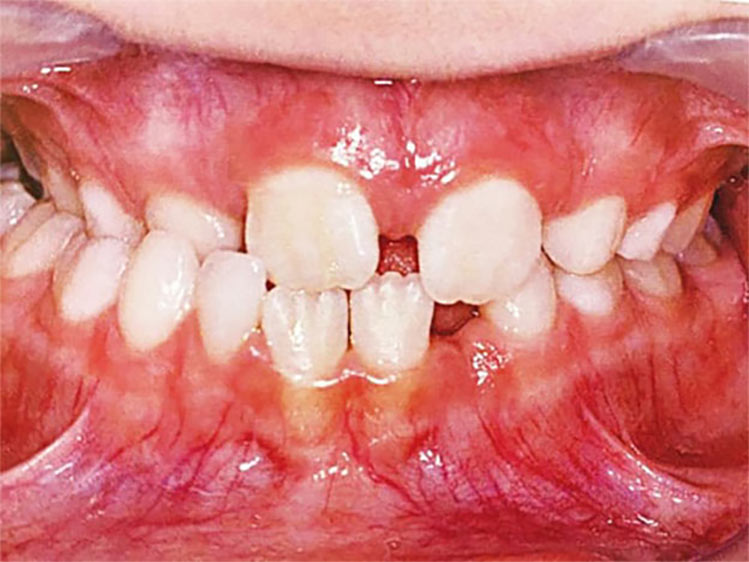

É necessário fazer uma avaliação clínica e radiográfica criteriosa da oclusão do paciente.

Se algo estiver fora da normalidade, o problema poderá ser interceptado e corrigido prontamente, evitando longos tratamentos ortodônticos no futuro.

As chances de correção de uma má oclusão é infinitamente maior quando é possível contar com o crescimento e desenvolvimento da criança.

Porque dentes apinhados acumulam mais alimentos, mais placa bacteriana, mais tártaro, mais inflamação de gengiva, sangramento, mau hálito e aumentando o risco de surgimento de cáries.